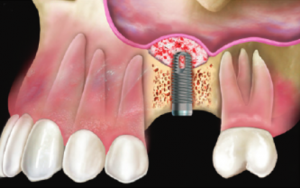

6. A questo punto viene inserito l’impianto, che viene stabilizzato grazie all’osso pre-esistente, ma che, nei mesi successivi, formerà un tutt’uno con l’innesto di osso. |

| Inadeguata quantità di osso residuo per inserire un impianto. | Con la tecnica del mini-rialzo l’impianto è stato inserito contemporaneamente al piccolo innesto di osso. |